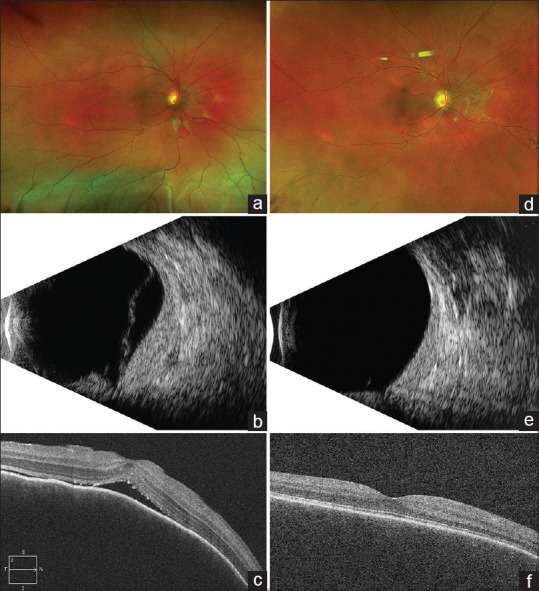

Purpose: To report outcomes in patients treated with low-dose lens-sparing intensity-modulated radiation therapy (IMRT) for diffuse choroidal hemangioma (DCH) associated subretinal (subfoveal) fluid (SRF).

Material and methods: Retrospective interventional case series. 10 patients (11 eyes) treated with IMRT for diffuse choroidal hemangioma-associated SRF. Resolution of subretinal fluid, tumor regression, and best-corrected visual acuity (BCVA).

Results: The mean age was 9.9 years (range, 0.3-32), with 8 (73%) having exudative retinal detachment in the right eye. The rationale for treatment was the presence of SRF (11 eyes, 100%). At baseline, the maximal height of the tumor was 3.4 mm (range, 1.7-5.3). The mean BCVA in the affected eye was 40 ETDRS letters (range, 5-75). All eyes were treated with IMRT (lens-sparing) at a dose of 20 Gy in 10 fractions. Patients were followed up for an average duration of 7 years (range 6-120 months), with 9 (82%) followed up for more than 2 years. Resolution of SRF was noted in all 11 (100%) eyes, with 6 (55%) eyes showing resolution within 3 months. Tumor response was observed in all eyes 11 (100%) (reduction or stabilization of tumor height), with the mean posttreatment height of 2.0 mm. BCVA improved or remained stable in 10 (91%). Radiation-related complications (cataracts, radiation retinopathy, radiation optic neuropathy) were not observed in any of the treated patients.

Conclusions: Low-dose lens-sparing IMRT is a highly effective treatment for diffuse choroidal hemangioma. IMRT resolves subretinal fluid, induces tumor regression, and preserves visual acuity in vast majority of cases.